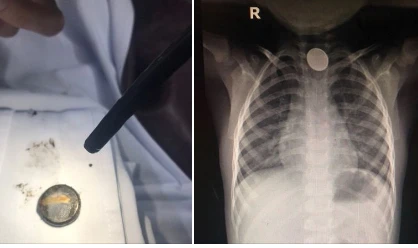

Trước đó, bé NHPT (TP.HCM) được đưa đến BV Thủ Đức trong tình trạng mệt mỏi, đau cổ họng, ho sặc sụa, ăn vào nôn ói… Nghi ngờ bé nuốt dị vật, các BS cho chụp X-quang và phát hiện dị vật kim loại hình tròn nằm tại vị trí 1/3 thực quản trên.

Pin sau khi lấy ra và hình ảnh pin nằm tại vị trí 1/3 thực quản trên. Ảnh: BVCC

Các BS nhanh chóng gắp dị vật và ghi nhận đó là cục pin đang rỉ sét. Điều đáng nói hóa chất trong pin rò rỉ ra ngoài gây bỏng, viêm loét cuống họng và thực quản của bé.